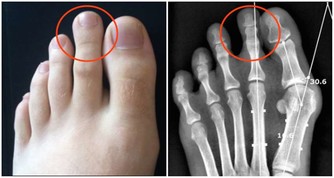

9. 狼瘡狼瘡是一種自身免疫性疾病,影響身體的許多系統和器官,皮膚也包含在內。該病的早期症狀之一,是在臉頰和鼻樑處出現蝴蝶形狀的紅棕色皮疹。當病情爆發時,皮疹看起來像是臉被曬傷了,這種皮疹的醫學術語是顴骨皮疹。狼瘡是一種需要看醫生的病症,它無法治愈,但治療可以幫助減少發作次數以及減少並發症。